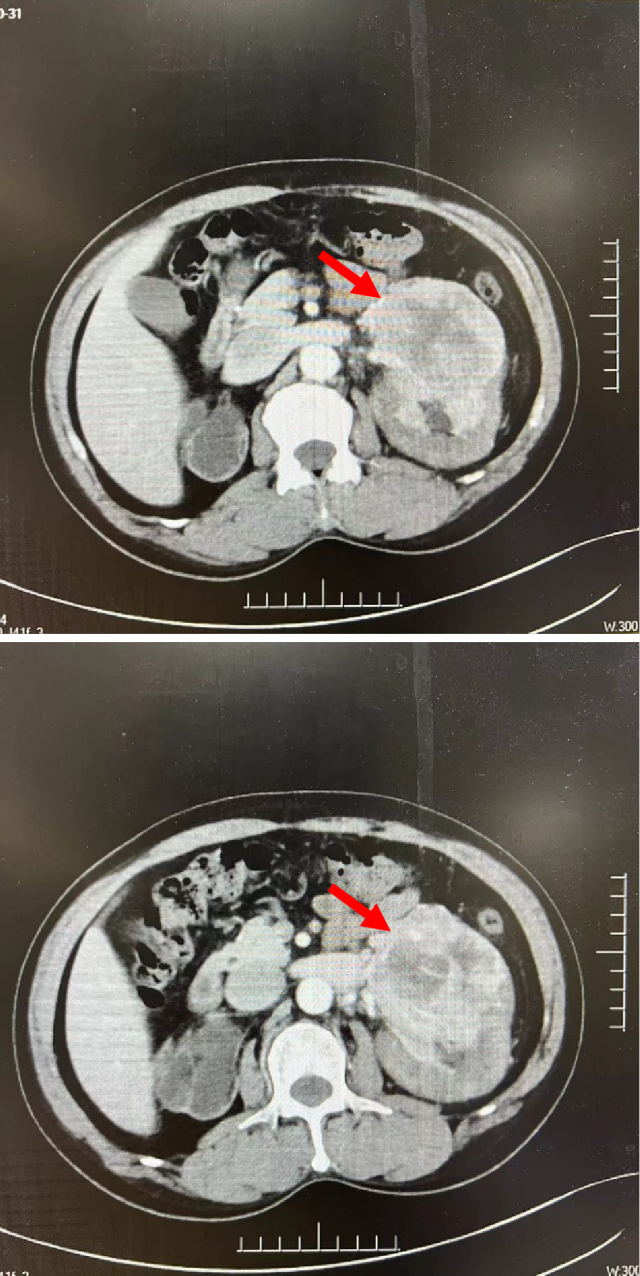

CT(2022.7):1. 右肺转移瘤切除术后改变;2. 左肾上腺结节,转移?3. 左肾多发结节,转移瘤?4. 腹膜后淋巴结肿大,转移可能;5. 左肾多发小囊肿。

2022.10 开始予以靶免联合治疗

PETCT(2022.10):1. 左侧肾上腺结节灶,糖代谢增高,转移瘤可能性大;2. 左肾多发结节状突起,糖代谢增高,考虑转移瘤,需结合增强 CT 综合判断;3. 右下肺切除术后,术区未见复发;4. 右侧胸壁局部增厚、糖代谢增高,术后改变?建议追踪。

靶免联合治疗 1 年后复查

CT(2023.7.17):1. 左肾上腺结节、左肾结节及肿块较前明显增大:转移?左肾 CA 并左肾内、肾上腺转移?2. 腹膜后淋巴结较前增大,转移可能;3. 余况基本同前。

2023.7 开始予以伏罗尼布单靶治疗

CT(2023.12.6):1. 左肾上腺结节较前稍缩小、左肾结节及肿块较前稍缩小;2. 腹膜后淋巴结转移灶同前;3. 余况基本同前。